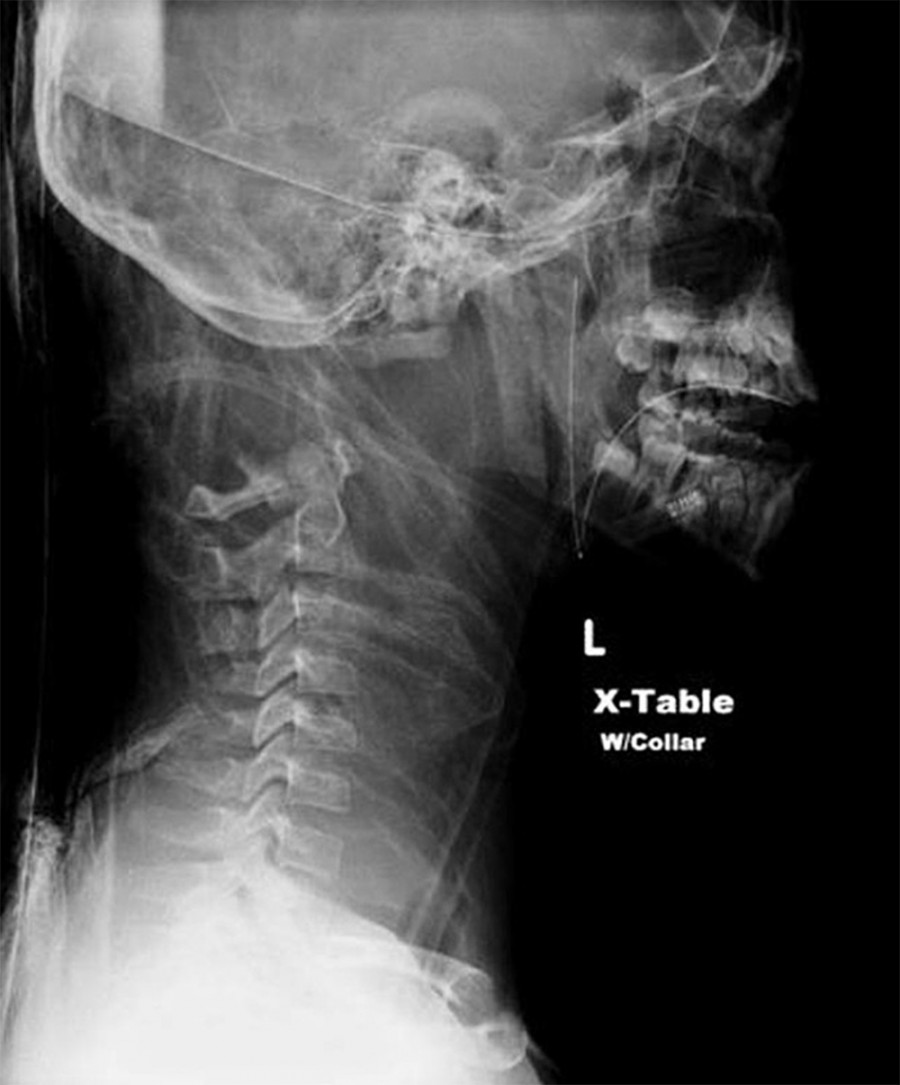

Zunanje obglavljenje poznamo iz zgodovine, kjer zunanja sila odseka glavo od telesa. Notranje obglavljenje pa je bolj redko in se zgodi takrat, ko je lobanja ločena od hrbtenice, vendar pa se še vedno drži telesa. To se lahko zgodi med naključnimi poškodbami ali pa namerno. In čeprav se sliši neverjetno, lahko ljudje poškodbo ob hitrem zdravniškem ukrepanju preživijo.